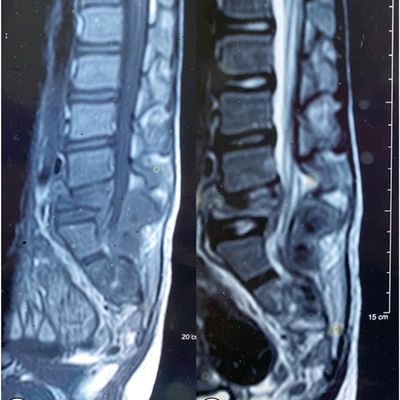

Click on an image below to view more info.